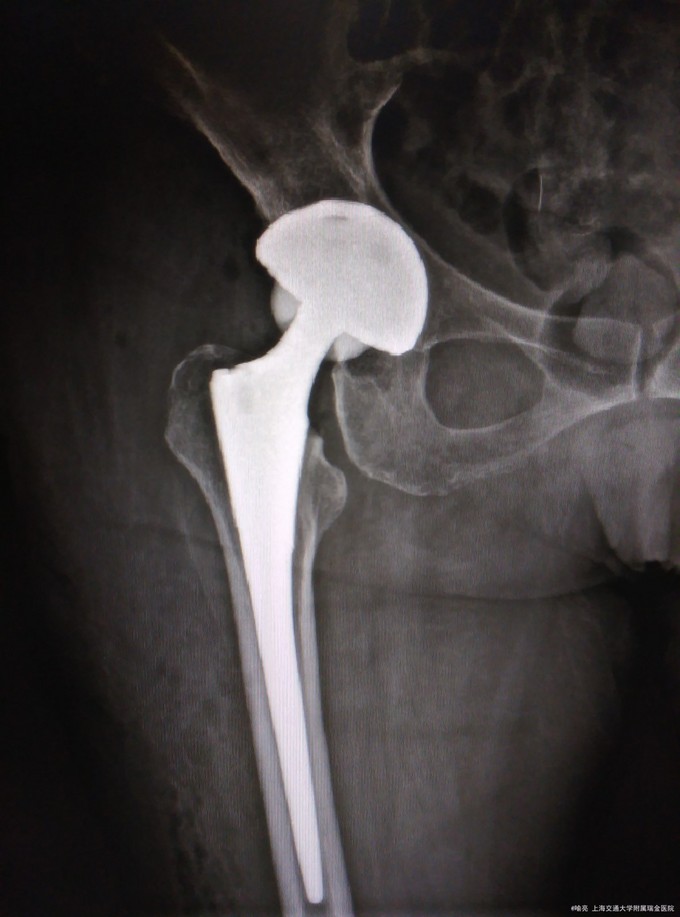

DDH继发髋关节退变 右侧THA

6周后复查患者右侧髋关节疼痛消失,活动度可。 由于DDH髋关节覆盖不足,只要髋关节前后壁是完整的,髋臼杯仍能固定稳定。适度得加深髋臼或上移髋臼杯可以增加髋臼德覆盖。